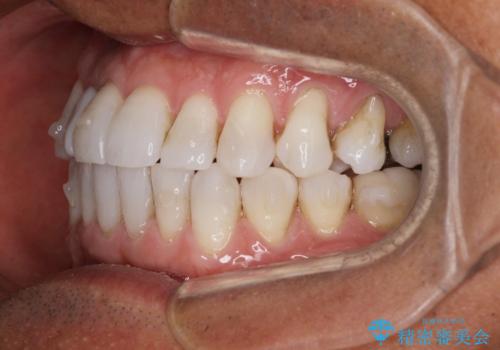

- 治療途中の前歯と上下前歯のデコボコ気にして来院された患者様です。

前歯のデコボコはインビザラインにより歯列を整え、その後に、前歯などをオーダーメイドタイプのオールセラミッククラウンにて補綴治療することとしました。

長時間のマウスピース装着に協力いただき、短期間で歯列をしっかりと改善することができました。

ホームホワイトニングを併用していただいたので、とても明るい口元に仕上がり、患者様には大変満足していただきました。